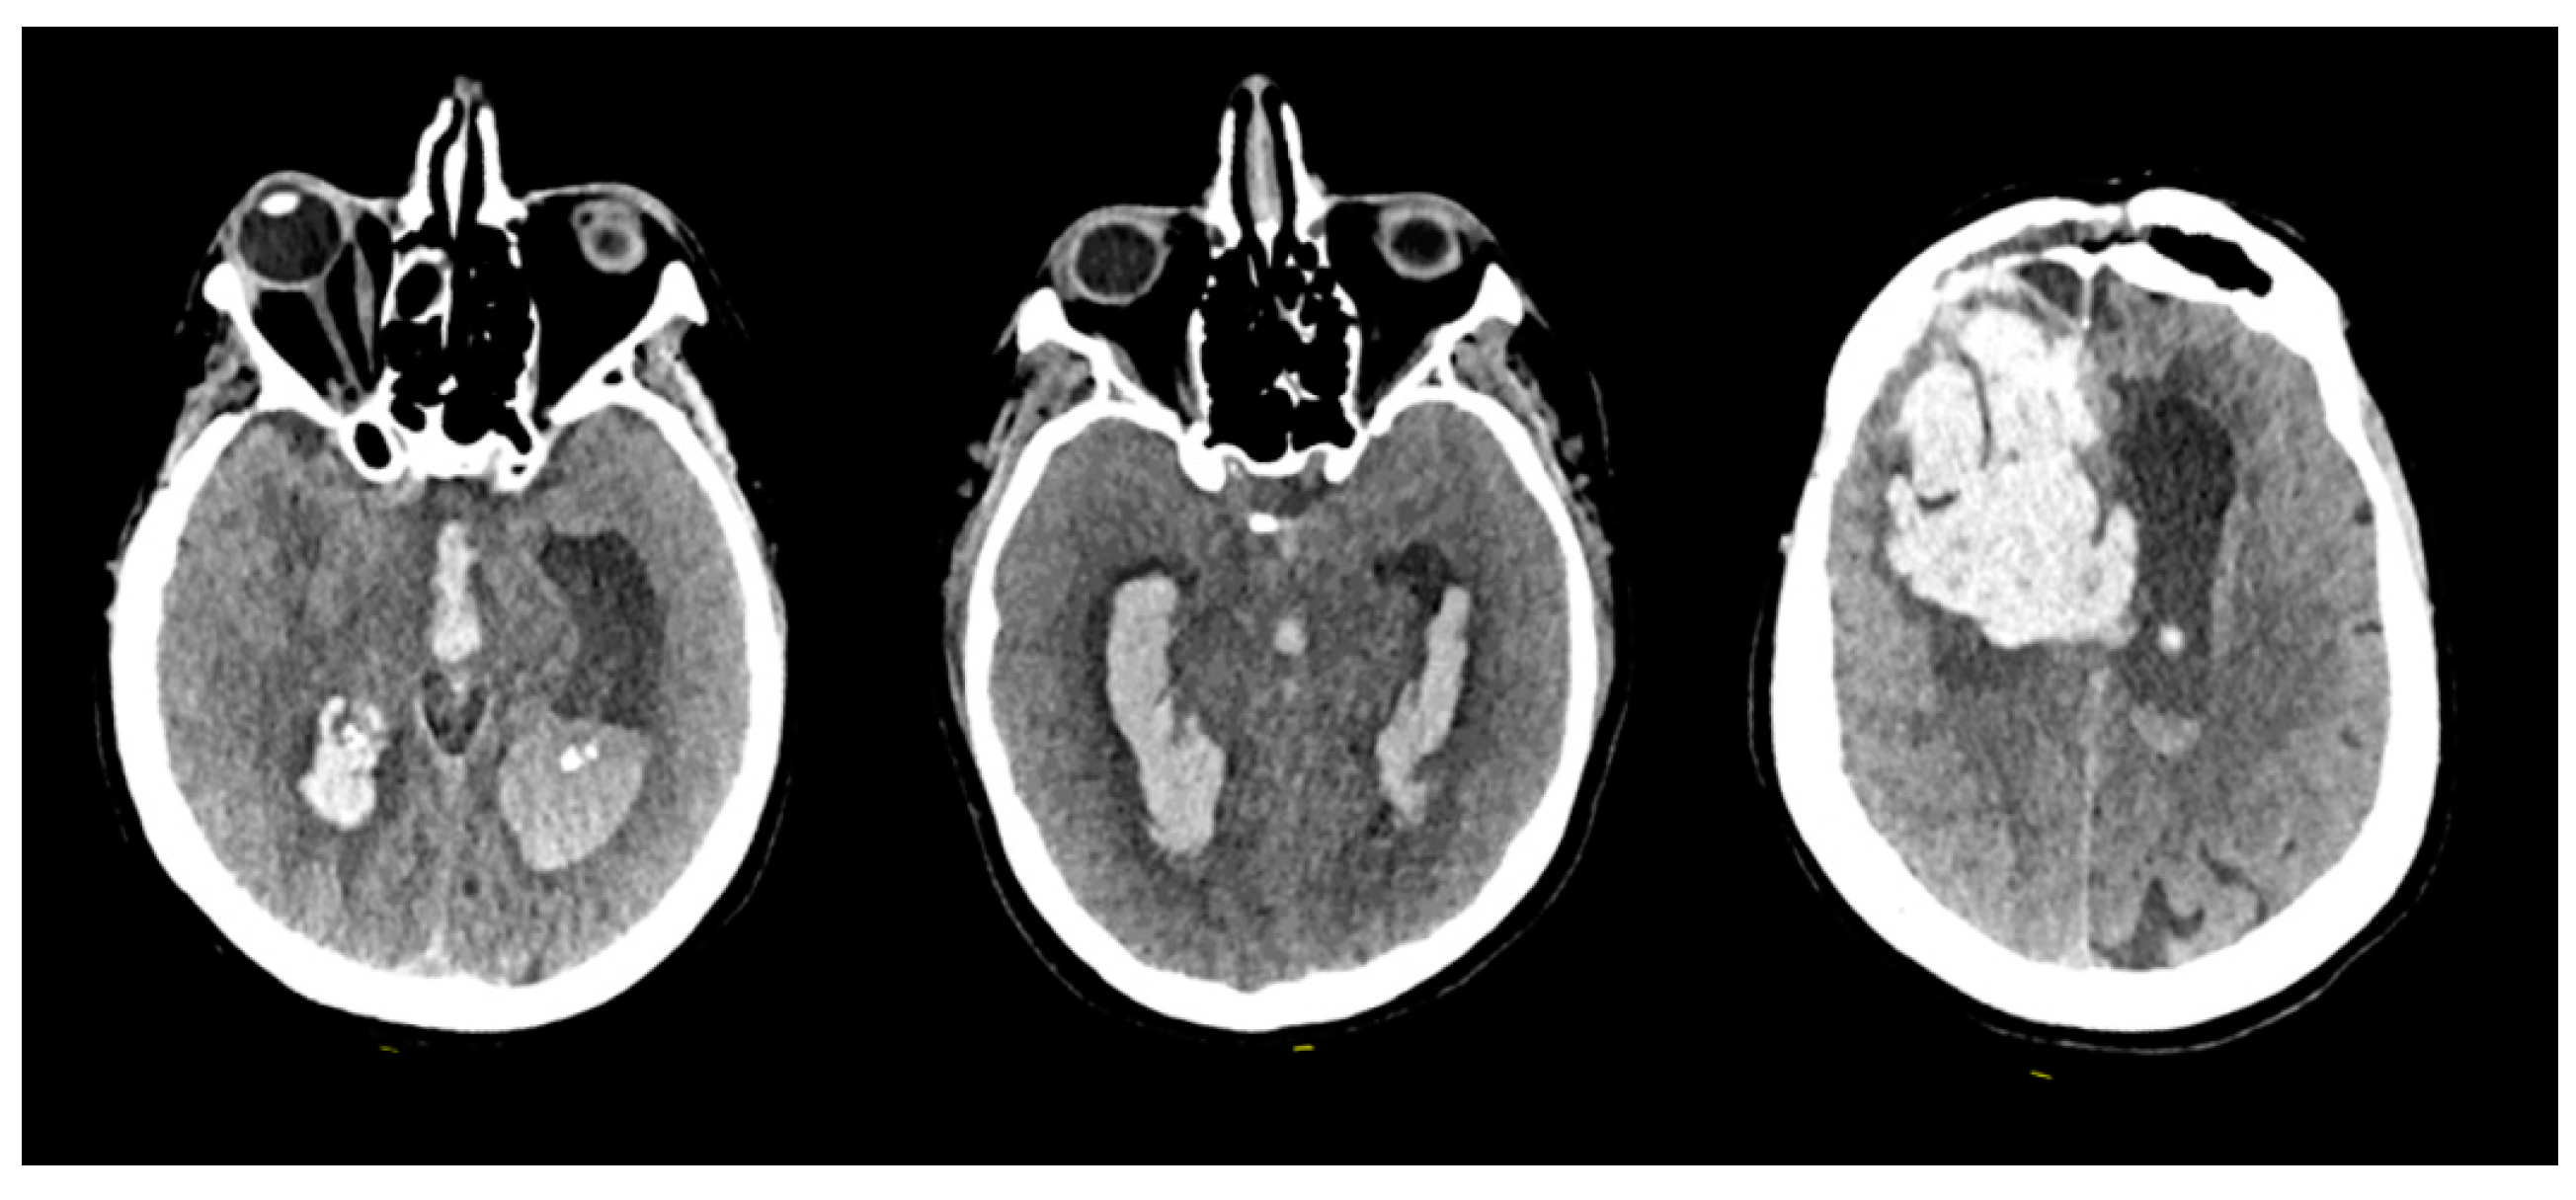

- The location of the hematoma was consistently distant from the arteriovenous malformation (AVM) nidus, surrounding the trajectory of the ventricular catheter.

- The occurrence of the hemorrhagic complication transpired several weeks after the initial AVM rupture and several days after the placement of the VPS.

- Catheter-related DICH manifested in all 10 cases without any evident coagulation disorders or other identifiable risk factors.